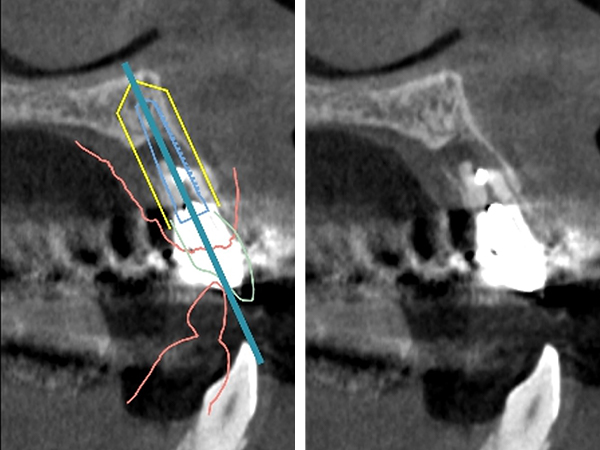

CTによる診査

CTを撮影し、歯根の長さや根尖病変の大きさを精査しました。

CTによるシミュレーション

2|

|1